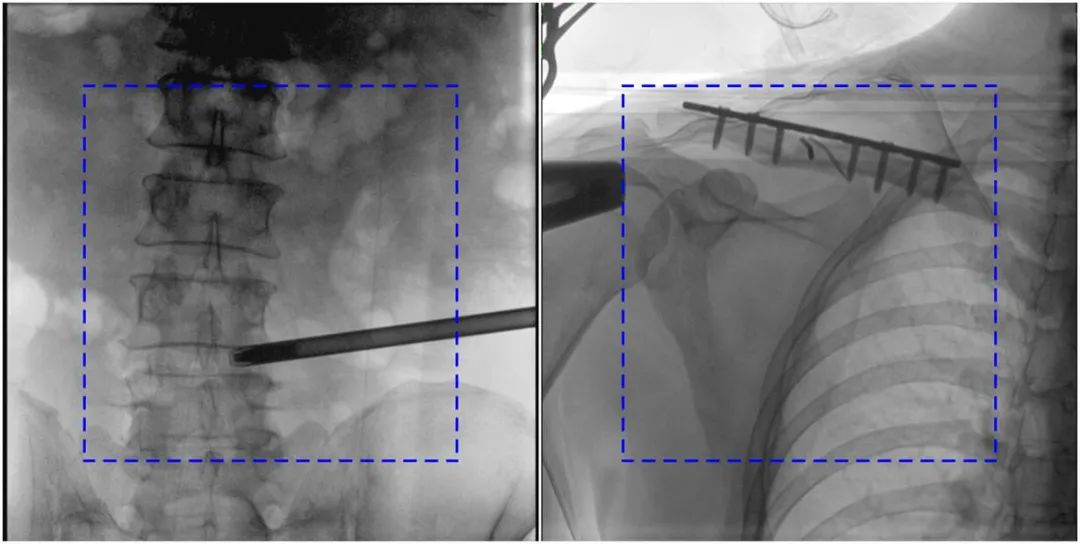

與傳統(tǒng)的21CM×21CM成像尺寸相比,普愛(ài)醫(yī)療大平板一體式C形臂具有30CM×30CM更大成像尺寸,能夠一次成像5.5節(jié)椎體,呈現(xiàn)更全面的影像信息,即便是手術(shù)經(jīng)驗(yàn)不豐富的年輕醫(yī)生也能通過(guò)圖像迅速判斷椎體節(jié)段、定位手術(shù)部位,避免因?yàn)橐曇安蛔愣斐傻亩啻味ㄎ?、反?fù)曝光,提高效率的同時(shí)避免過(guò)量攝入輻射。

普愛(ài)醫(yī)療大平板一體式C形臂圖像與傳統(tǒng)圖像對(duì)比(藍(lán)色虛線內(nèi)為傳統(tǒng)21CM×21CM平板的成像區(qū)域)